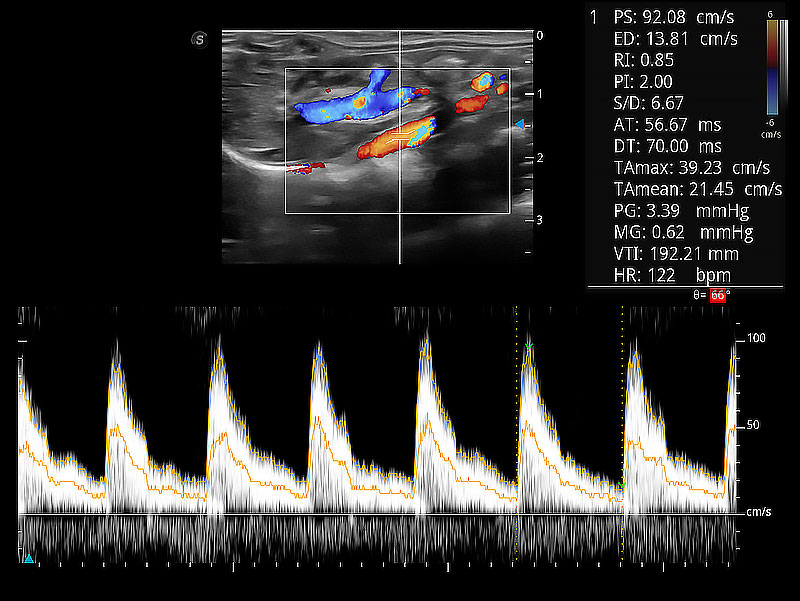

隨著取樣門(mén)位置改變,頻譜多普勒包絡(luò)可進(jìn)行自動(dòng)眼蹤測(cè)量,且可自由配置測(cè)量的參數(shù)。